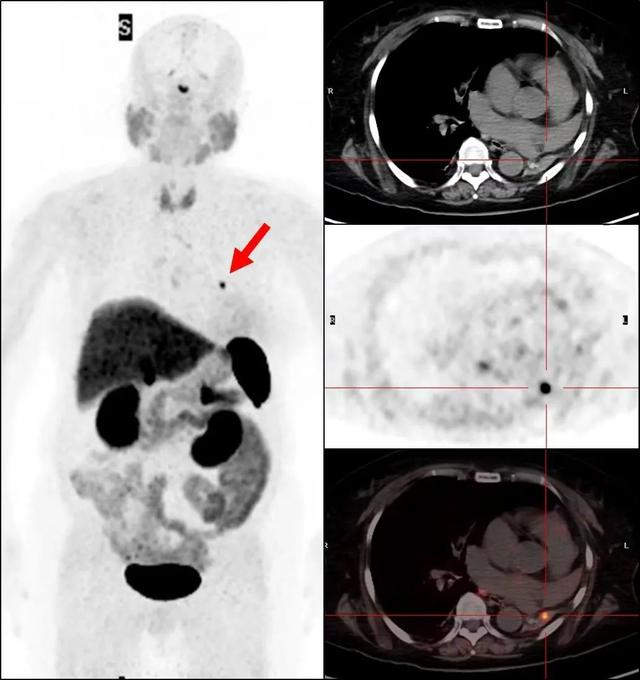

检查完的第二天,主管医生告诉范阿姨病灶找到了!范阿姨原本左肺先天性发育不良,就在她萎缩的左肺里找到了一枚微小结节,直径约1cm,在68Ga-DOTATATE PET/CT显像中有明显的放射性浓聚,SUVmax达14.8。随后范阿姨被转到了胸外科手术,李鹤成主任进行了“胸腔镜辅助左肺切除术”,手术病理证实确实为分泌ACTH激素的支气管类癌。手术之后范阿姨的皮质醇水平明显下降,半年后回医院复查病情得到了痊愈。